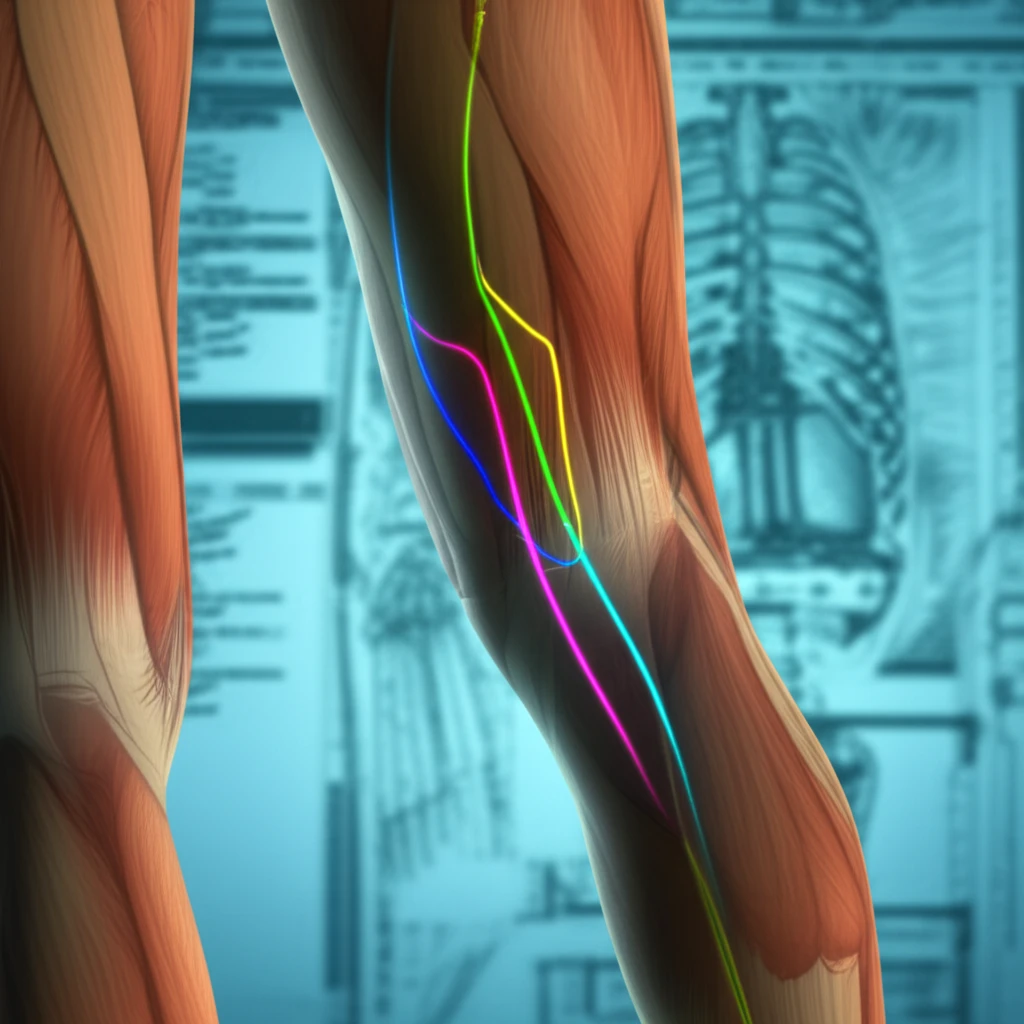

The distally based sural flap has emerged as a workhorse in reconstructive surgery for this area, offering a reliable solution for covering deep tissue defects. This fasciocutaneous flap relies on the sural artery and its perforators, making a thorough understanding of its anatomy crucial for successful outcomes.

- Sural Nerve as a Guide: The sural nerve was consistently identified in all dissections, serving as a reliable landmark for locating the vascular pedicle.

- Perineural Plexus Dominance: In a significant number of cases, the primary blood supply to the flap originated from a perineural plexus surrounding the sural nerve.

- Arterial Variations: The study observed variations in the sural artery's presentation, including the presence of three distinct sural arteries (lateral, median, and medial) in some dissections, while others exhibited only lateral or combined lateral and medial arteries.

- Perforator Distribution: The number of perforating arteries varied, with 3 to 6 perforators identified on the medial side of the pedicle and 4 to 5 on the lateral side.

The study's findings emphasize the variable nature of the sural artery's distribution, with the perineural plexus being a common source of blood supply. This suggests that flap design should prioritize the inclusion of the sural nerve and its surrounding tissue to maximize vascularity.

Based on the perforator mapping, the pivot point of the flap—the point around which the flap is rotated—should be approximately 5.5 cm above the lateral malleolus. This positioning optimizes the inclusion of key perforating arteries in the flap's pedicle.